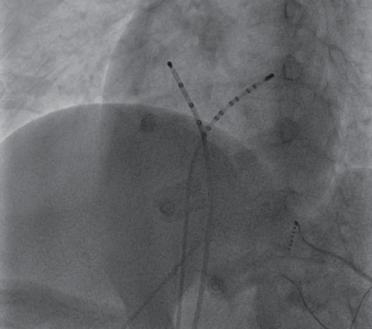

(6)经股动脉鞘送入冠状动脉造影导管行冠状动脉造影,以观察消融导管与冠状动脉的距离,确认消融靶点部位避开冠状动脉后(图2-4-3),起搏并确认避开膈神经位置,放电消融至室速终止。

图2-4-3 行冠状动脉造影确定靶点远离冠状动脉